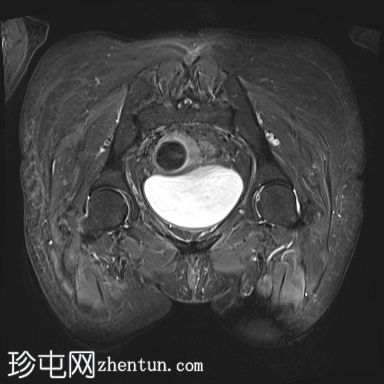

轴位

DWI

中下段直肠肿块,形态不规则,边缘清晰,质地不均一,以囊性为主,多分叶,增强扫描时实性部分强化,弥散不受限,病灶下缘位于肛门直肠连接处30毫米处,呈半圆形,横跨半径3点至9点方向,纵轴长约44毫米,向直肠系膜脂肪方向延伸达15毫米,但未超过直肠系膜筋膜。直肠上段无改变。未观察到淋巴结肿大。

此外,可见子宫呈前屈状,外观不均匀,内部信号低,呈卵圆形,边缘清晰,造影剂应用后出现不均匀强化,从而影响了子宫内膜的体积效应。子宫横、前后和头尾方向的尺寸分别为 2.9 x 2.8 x 4.0 cm,与黏膜下肌瘤相关。

病理报告证实为高分化 G1 肠腺癌。患者已接受放疗和化疗。肿瘤分类为 T3。